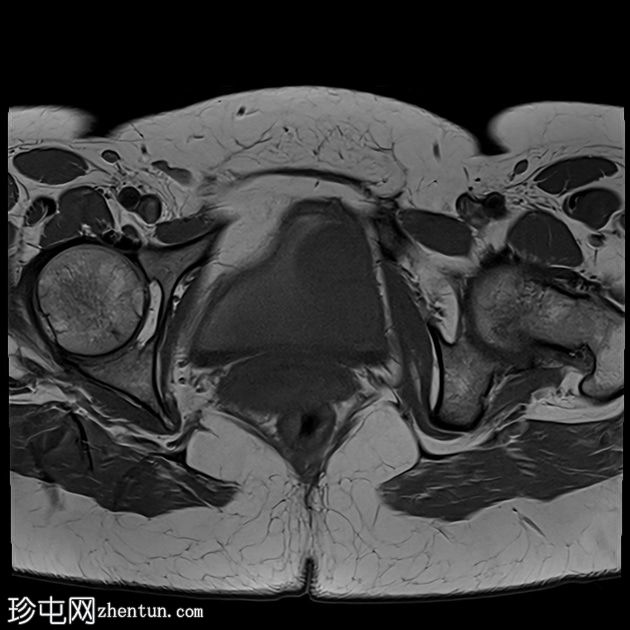

轴位

T1加权像

可见膀胱左侧壁有一边界清晰的T2低信号实

性病

灶,无扩散受限,均匀强化。未见膀胱周围侵犯或肾积水。

子宫底部前壁可见一小肌瘤。双侧卵巢可见无强化囊肿。盆腔及腹股沟未见异常淋巴结肿大。

这是一例经组织学证实的膀胱平滑肌瘤病例。